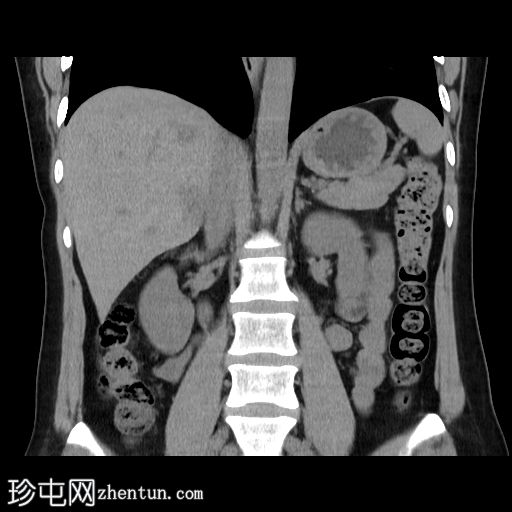

冠状面

非造影

6.jpg

冠状面C+期

动脉期

在轴向、冠状面和矢状面上均可见肝5/6段病变。动脉期可见周围结节状强化,门静脉期可见进行性向心性充盈,延迟期亦持续存在。这些表现为肝血管瘤的特征性表现。

然而,目前的CT扫描显示动脉期呈周围结节性强化,门静脉期呈进行性向心性充盈,且延迟成像后仍持续存在。这些特征是肝血管瘤的特征。未发现其他肝脏病变。